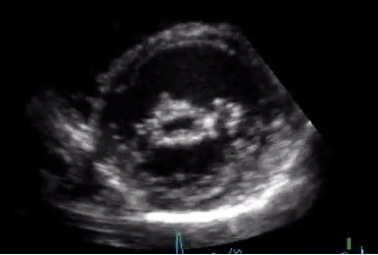

Vad ser du på denna bild?

Vad ser du på bilden?

Vad ser du?

Förmodad urinblåsetumör